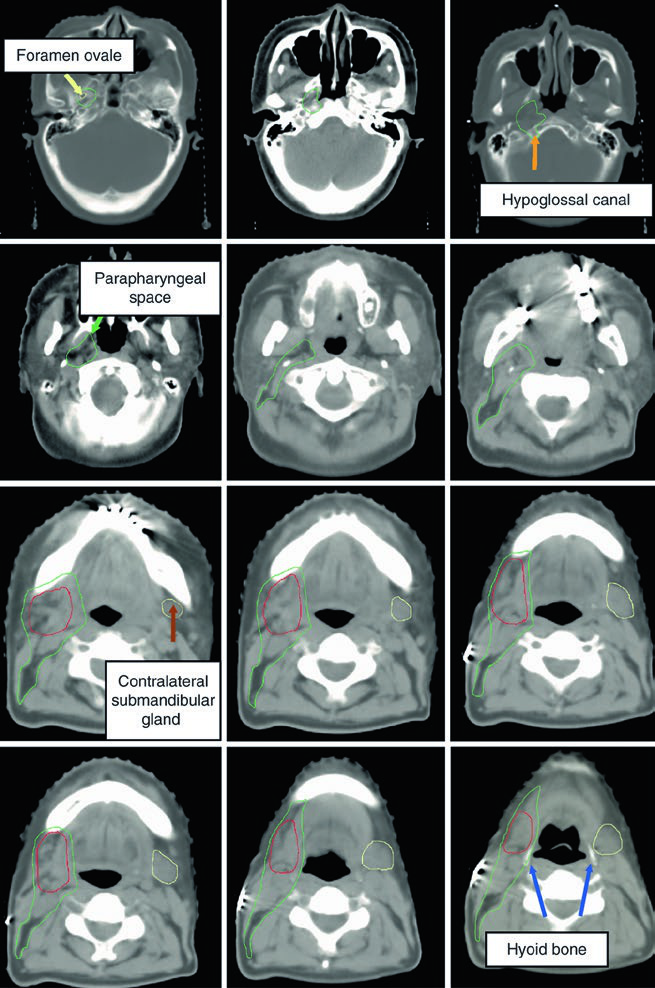

A imagem mostra um caso de carcinoma mucoepidermoide de alto grau cT1N1M0 da submandibular direita, com o CTV60–66 (vermelho) cobrindo o leito cirúrgico e o CTV50–54 (verde) englobando estações nodais ipsilaterais e o espaço parafaríngeo até a base do crânio. Essa abordagem garante cobertura adequada mesmo em tumores de estádio inicial mas alto grau.

As imagens da TC demonstram o trajeto do nervo glossofaríngeo em diferentes cortes axiais. O nervo pode ser identificado posterolateral ao processo estiloide, descendo junto à carótida interna. A marcação oval vermelha nos cortes mostra a localização esperada do nervo ao longo de seu percurso cervical. O último corte utiliza janela de partes moles para melhor visualização das relações entre o nervo e os vasos cervicais.